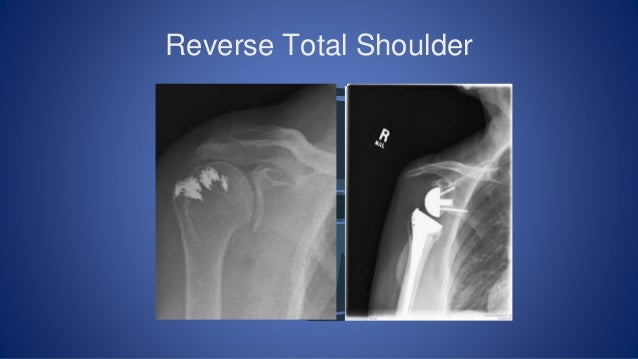

An Owners Guide To Shoulders

An Owners Guide to Shoulders www.slideshare.net